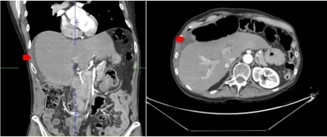

Figure 1: Post-cholecystectomy scan show perihepatic fluid (red arrow).